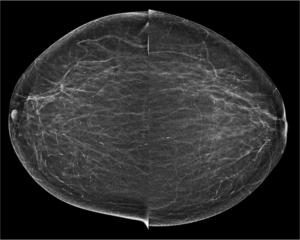

Cranio caudal view: Focal cluster of punctate microcalcifications seen in left sub areolar region- Indeterminate. On Tomosynthesis: In the given slice of tomosynthesis the calcifications are clearly seen and also the skin pores are well made out in the same section which confirms that the calcifications are in the plane of skin. Hence the calcifications are benign. No further views/ management required.